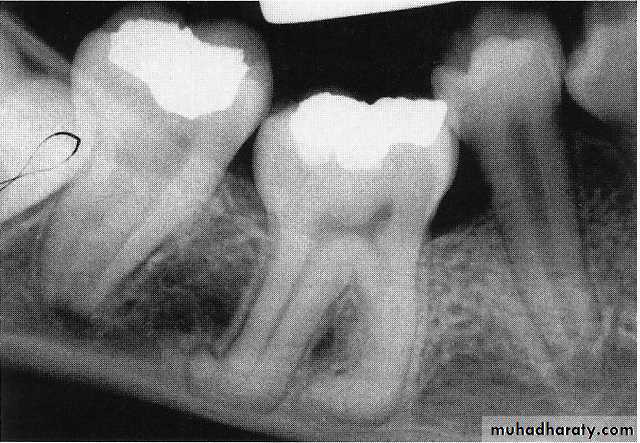

A, Pulp of the fi rst permanent molar was exposed by caries. The tooth was considered a candidate for the calcium hydroxide pulpotomy technique.

B, Calcifi ed

bridge has formed over the vital pulp in the canals.C, Continued

root development and pulpal recession are indicative of continuing pulpal vitality. The crown should be supported with a full-coverage restoration.Mature and immature teeth in the x-ray

Internal resorption after calcium hydroxide pulpotomy in a primary tooth

Deep caries in the first primary molar and due to that caries resorption in the bifurcation areaDeep caries in the mandibular second primary molar